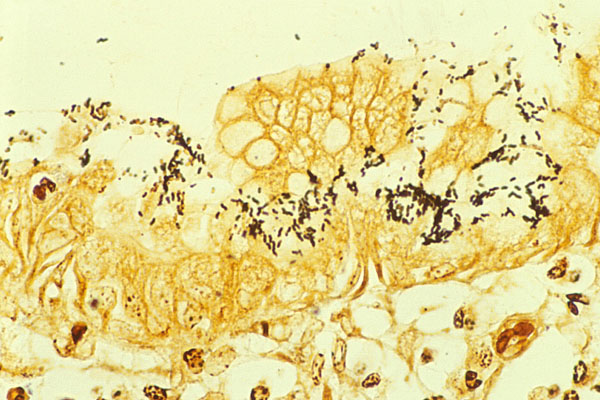

📌 Warthin Starry

يتم استخدامها للتشخيص باكتيريا

Spirochaete and H pylori

والنتيجة عندنا تظهر عندنا بالاسود للأثنين

اما بالنسبة الأنسجة يكون لونها اصفر الى البني